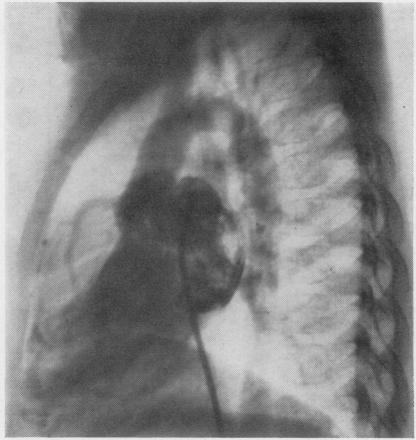

Phonocardiography is of great importance in distinguishing coronary artery fistula from other anomalies with a continuous murmur. The presence of this murmur at the apex must be regarded as an important characteristic of a coronary artery fistula, especially when the maximum diastolic murmur is found at the apex. Although coronary artery fistula may be symptomless for a long time, surgical treatment is desirable in most cases. Extracorporeal circulation should be used in all operations for coronary artery fistula to avoid ligation of the wrong artery or failure to close all fistula orifices.

心音图对于鉴别冠状动脉瘘与其他伴有连续性杂音的异常情况极为重要。在心尖部出现这种杂音必须被视为冠状动脉瘘的一个重要特征,尤其是当在心尖部发现最大舒张期杂音时。尽管冠状动脉瘘可能长期无症状,但在大多数情况下仍需要进行手术治疗。所有冠状动脉瘘手术均应使用体外循环,以避免结扎错误的动脉或未能闭合所有瘘口。